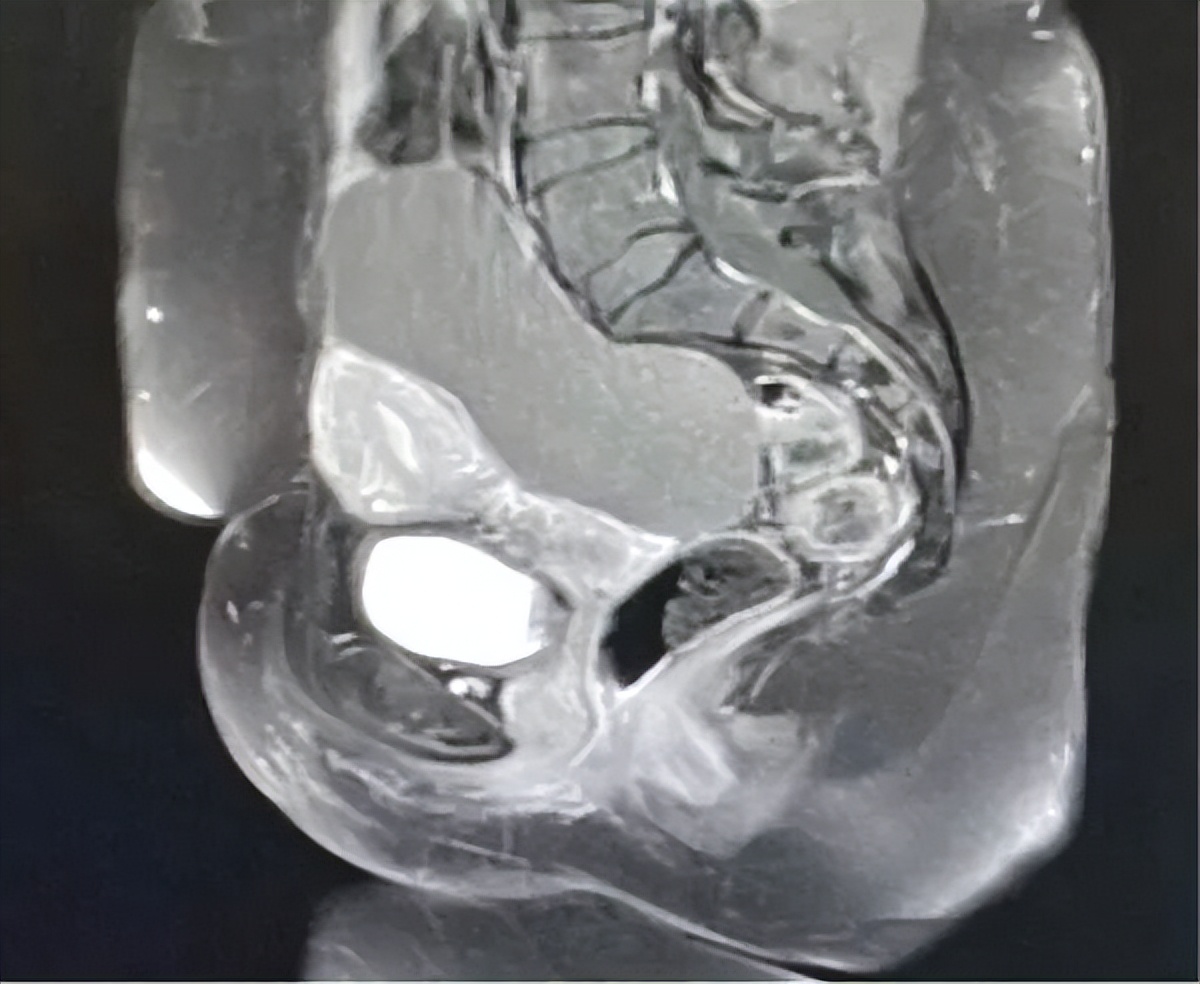

为了进一步评估病灶特征,患者进行了MRI检查,确认右侧附件区有一个边界清晰的囊性病变,大小为12×10×6 cm。病变主要为液性,表现为T1低信号、T2高信号。其内部结构为多房性,伴有少量薄而光滑的分隔,并包含一小块T1高信号、T2低信号区的病灶(在脂肪抑制序列上未被抑制),符合陈旧性出血的表现。增强扫描仅显示有薄的、轻微的分隔强化,无实性强化结节、不规则/增厚分隔(>3 mm)或坏死证据。解剖学上,囊肿与邻近盆腔结构分界清晰,无侵袭征象。基于这些特征(囊内容物为单纯液体、分隔薄而光滑、无实性成分),该病变经影像学评估为良性复杂性囊肿,如囊腺瘤或出血性囊肿(图1和图2)。

图1.增强磁共振成像显示右侧附件/卵巢有一个边界清晰的大囊性病变,大小为12×10×6 cm

图2.增强磁共振成像显示多房性病变,伴有少量薄层光滑的分隔